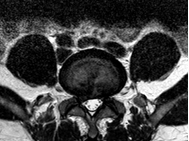

主诉:腰部疼痛1年余,伴左下肢疼痛麻木3月。 病史:女性患者,53岁。患者1年余前在做家务时出现腰部剧烈疼痛,当时腰部活动受限,在外院门诊诊断为腰肌劳损,给予对症治疗,效果较好。1年余来活动后腰部均出现疼痛,反复出现。最近3年以来,患者腰部疼痛时间延长,加重,并伴左下肢麻木,放射痛至足踝处。患者一般情况尚可。

查体:腰4/5、腰5/骶1棘间及左右棘旁轻压痛、叩击痛,左侧坐骨神经出口处明显压痛。左小腿外侧感觉略减退,左侧伸膝、踇背伸肌力4级,左侧直腿抬高试验20°(+),加强(+),Lasegue征(+),左侧4字征(+),左侧股神经牵拉试验(+)。双侧Babinski 征及Oppenheim 征(-)。 辅助检查:三大常规、血生化、肝肾功能均未见明显异常。患者腰椎动力位片正常,其余重要腰椎影像学如下。

诊断:腰椎间盘突出症(L4/5) 治疗:患者入院后尽快完善相关检查,患者目前腰椎稳定性尚可,暂拟”椎间孔镜微创“治疗。